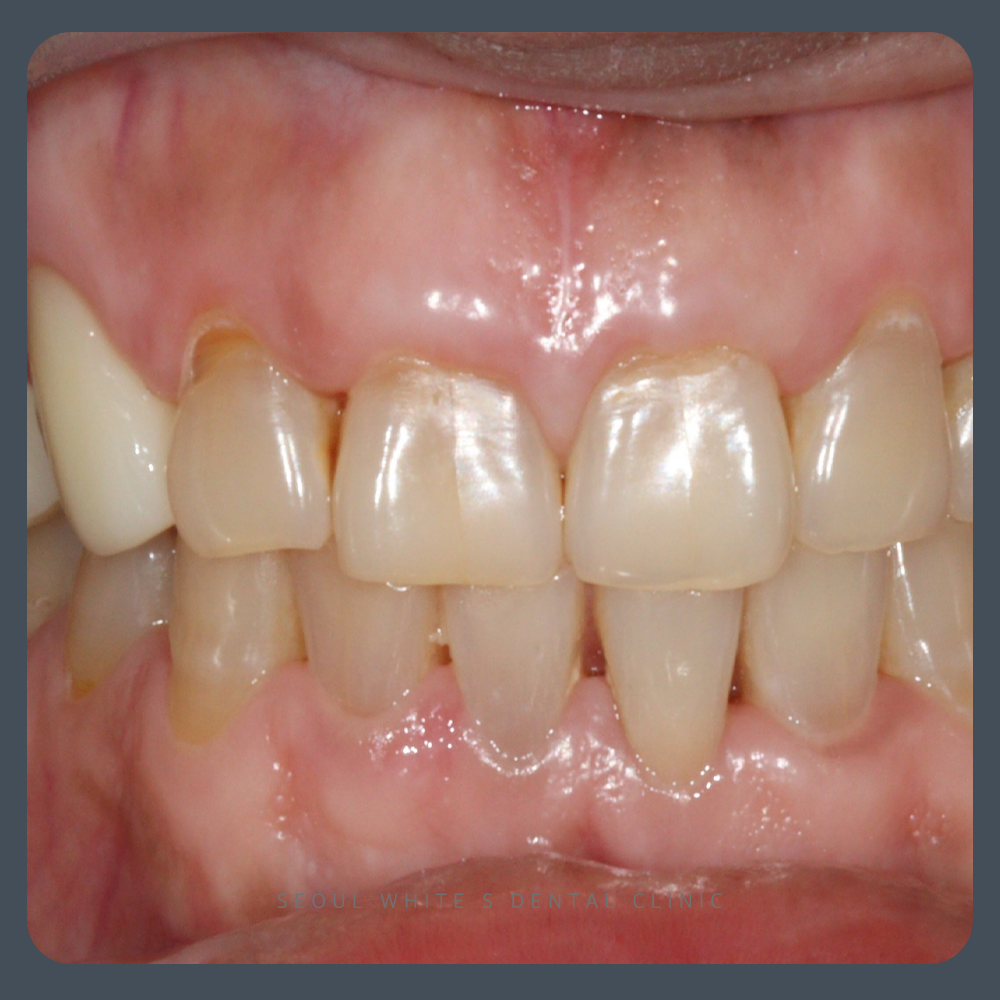

환자분은 몇 년 전부터 양치 중 출혈과 잇몸 붓기를 반복하다가, 최근에는 통증과 간지러움이 생겨서 내원하셨습니다.

환자분께서는 특히 하악 전치부(아랫니 앞부분) 쪽은 부풀고 간지러운 느낌이 지속되어 생활에 큰 불편 느끼고 계셨습니다 염증으로 인한 잇몸 조직의 손상을 줄이고, 세균과 노폐물이 다시 쌓이지 않도록 관리하는 데 중점을 둔 치료입니다. 하지만 이미 치아 주위의 뼈가 파괴된 경우, 이를 치료만으로 온전히 되살리는 것은 어렵습니다. 그렇기 때문에 조기에 발견하고 대응하는 것이 가장 중요합니다. 그렇다면 염증이 있는 상태를 그대로 두면 어떻게 될까요?

염증을 많이 가라앉히고 남은 뼈를 최대한 보존하여, 치아를 유지하였습니다! 염증으로 인한 잇몸 조직의 손상을 줄이고, 세균과 노폐물이 다시 쌓이지 않도록 관리하는 데 중점을 둔 치료입니다. 하지만 이미 치아 주위의 뼈가 파괴된 경우, 이를 치료만으로 온전히 되살리는 것은 어렵습니다. 그렇기 때문에 조기에 발견하고 대응하는 것이 가장 중요합니다. 그렇다면 염증이 있는 상태를 그대로 두면 어떻게 될까요? 경험상, 잇몸 질환에서 발생하는 염증은 저절로 사라지지 않으며, 시간이 갈수록 진행성이 강해져 상태가 더 나빠지는 경우가 많습니다.

잇몸이 안정된 이후에는 정기적인 유지 치료와 함께 치아 사이사이에 남아 있는 플라그 관리, 그리고 보조 구강위생용품 사용법도 함께 안내드렸습니다.